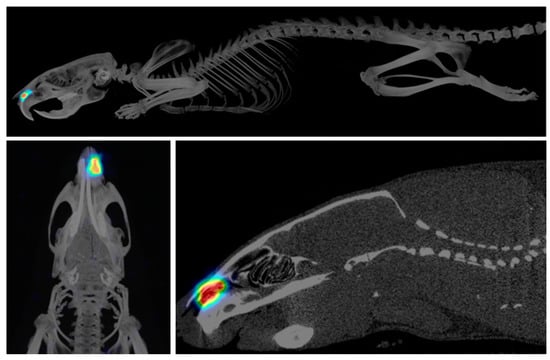

2. Materials and Methods

2.7. Microimplant Intranasal Administration and In Vivo Release Studies

3.3. In Vivo and In Vitro Release Studies